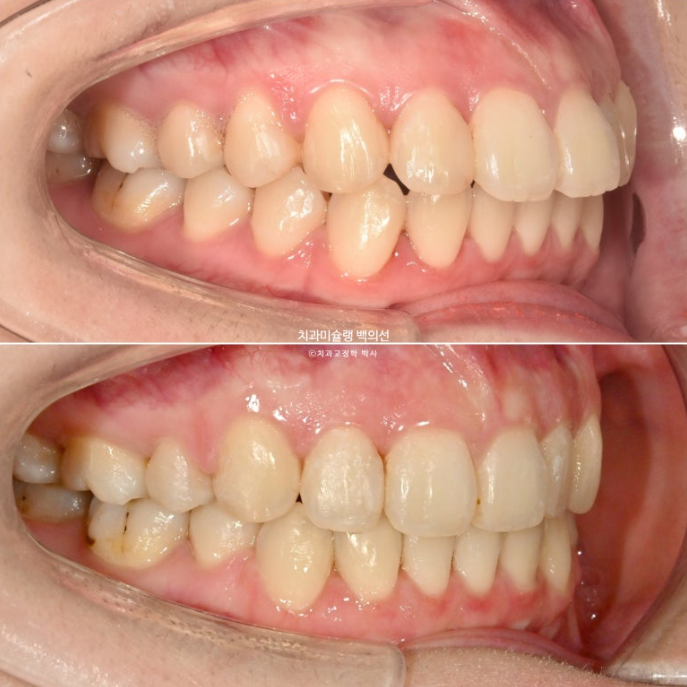

이제 전후비교 보겠습니다.

총 치료기간은 2년 2개월, 재제작은 1회 했습니다.

23.07~25.09

유지장치까지 들어간 모습이죠.

턱끝의 울퉁불퉁했던 호두주름이 사라졌습니다.

입은 한결 편하게 다물리며 입술이 처음에 비해 얇아진게 보입니다.

입술 얇아짐은 돌출입 발치교정에서 피할 수 없는 부분이나, 환자분의 초진시 원래 입술이 도톰하여 얇아짐이 부작용으로써 나타나진 않았습니다.

비로소 편하게 다물리는 입술을 보니 제가 다 편안합니다.

주목할만한 점은 턱끝의 모양 변화

돌출이 개선되어 입술부전증이 해소되면서 턱끝이 불필요한 긴장이 풀린 것도 턱선 변화에 한몫 하지만

아래 엑스레이 중첩에서 보듯 상악 전체치열 함입으로 하악골 자가회전이 일어나 실제로 턱끝이 전방으로 나왔습니다.

거미스마일은 완전히 해소되었으며 스마일라인와 입동굴은 적절합니다.

예쁜 앞니 각도가 돋보이네요.